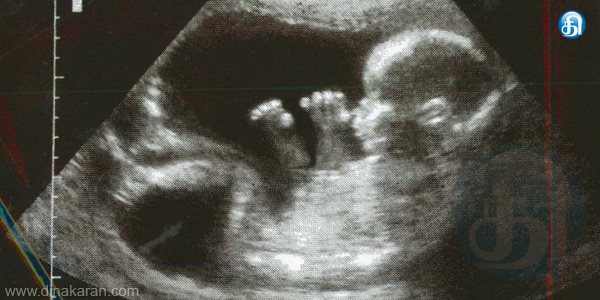

சென்னை: தமிழகத்தில் பெண் குழந்தைகள் பிறப்பு சதவீதம் குறைந்து வருவதாகவும், கருவிலேயே கண்டறிந்து அழிக்கப்படுவதே இதற்கு காரணம் என சமூக அமைப்புகள் குற்றம் சாட்டியுள்ளனர். தமிழகத்தில் செயல்படும் மனித ஆர்வலர்களுக்கான அமைப்புகள் சமீபத்தில் தகவல் அறியும் உரிமை சட்டத்தின் கீழ் அரசிடம் கேட்டு பெற்ற தகவல் அதிர்ச்சியை ஏற்படுத்தி உள்ளது. கடந்த 2011ம் ஆண்டு மக்கள் தொகை கணக்கெடுப்பின் படி 6 வயதிற்குட்பட்ட பெண் குழந்தைகளின் பாலின விகிதம் சென்னை மாவட்டத்தில் 21 புள்ளிகள் குறைந்து 950 ஆகவும், திருவள்ளூர் மாவட்டத்தில் 8 புள்ளிகள் குறைந்து 946 ஆகவும், காஞ்சிபுரம் மாவட்டத்தில் 2 புள்ளிகள் குறைந்து 959 ஆகவும் உள்ளது. இந்த பாலின விகிதம் இயற்கையாக 985 ஆக இருக்க வேண்டும்.

ஆனால், மிக குறைவாக உள்ளதாக தெரிய வந்துள்ளது. கருவிலேயே குழந்தை ஆணா, பெண்ணா என கண்டறிந்து பெண் குழந்தை என்றால் அதை கருவிலேயே கலைத்துவிடும் போக்கு பெருகி வருவது தான் இதற்கு காரணம் என இந்த அமைப்புகள் குற்றம்சாட்டி உள்ளன. மேலும், இந்த கொடிய செயலுக்கு ஸ்கேன் மையங்கள் துணைபோவதுடன், சட்டத்தை மீறி ஆண், பெண் குழந்தைகள் பற்றிய தகவலை தெரிவிப்பதும் முக்கிய காரணமாக கூறப்படுகிறது. இந்த அமைப்பினர் 2012ம் ஆண்டு பிறப்பு விகிதம் குறித்து கேட்டதற்கு தகவல் ஆணையம் அளித்த பதிலில் தமிழகத்தில் 1000 ஆண் குழந்தைகளுக்கு 952 பெண் குழந்தைகள் உள்ளதாக தகவல் தெரிவிக்கப்பட்டுள்ளது.

இதில், 18 மாவட்டங்களில் மாநில சராசரி அளவை விட குறைவாக இருப்பதும் தெரியவந்துள்ளது. குறிப்பாக 3 மாவட்டங்களில் பெண் குழந்தை பிறப்பு விகிதம் 900க்கும் குறைவு. காஞ்சிபுரத்தில் 914, விழுப்புரத்தில் 889, கடலூரில் 896 ஆக உள்ளது. உலகில் பல்வேறு துறைகளில் பெண்கள் சாதனை புரிந்து வரும் நிலையில், கடந்த சில ஆண்டுகளாக தமிழகத்தில் பெண் குழந்தைகள் பிறப்பு விகிதம் குறைந்து வருவது அதிர்ச்சியை ஏற்படுத்தி உள்ளது. எனவே, குழந்தை பிறப்பதற்கு முன் கருவின் பாலினத்தை அறியும் யுக்திகள் தடை சட்டம் 1994ஐ கடுமையாக நடைமுறைப்படுத்த வேண்டும். இல்லையேல் தமிழகத்தில் வருங்காலத்தில் பெண் குழந்தைகள் விகிதம் பெருமளவில் குறையும் நிலை ஏற்படும்.